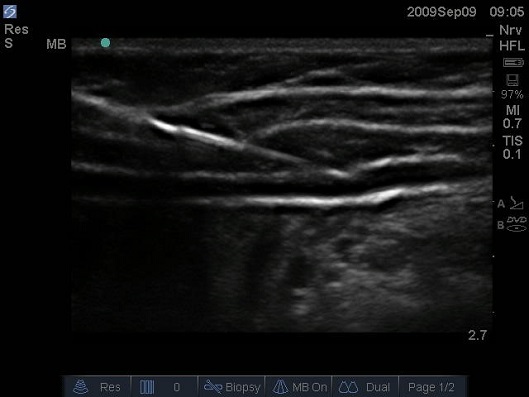

A linear transducer is placed alongside the lower margin. There are several different approaches for ultrasound guided tap block such as lateral posterior and subcostal approaches. The innervation to abdominal skin muscles and parietal peritoneum will be interrupted.

Traditionally the posterior tap block is performed at the triangle of petit. The transverse abdominis plane tap block is a peripheral nerve block designed to anesthetize the nerves supplying the anterior abdominal wall t6 to l1. For the lateral tap block a linear transducer is placed in.

12 this is an area bounded by the latissimus dorsi muscle posteriorly the external oblique muscle anteriorly and the iliac crest inferiorly the base of the triangle. It has a high margin of safety and is technically simple to perform especially under ultrasound guidance. A needle is inserted perpendicular to all planes looking for a tactile endpoint of two pops.